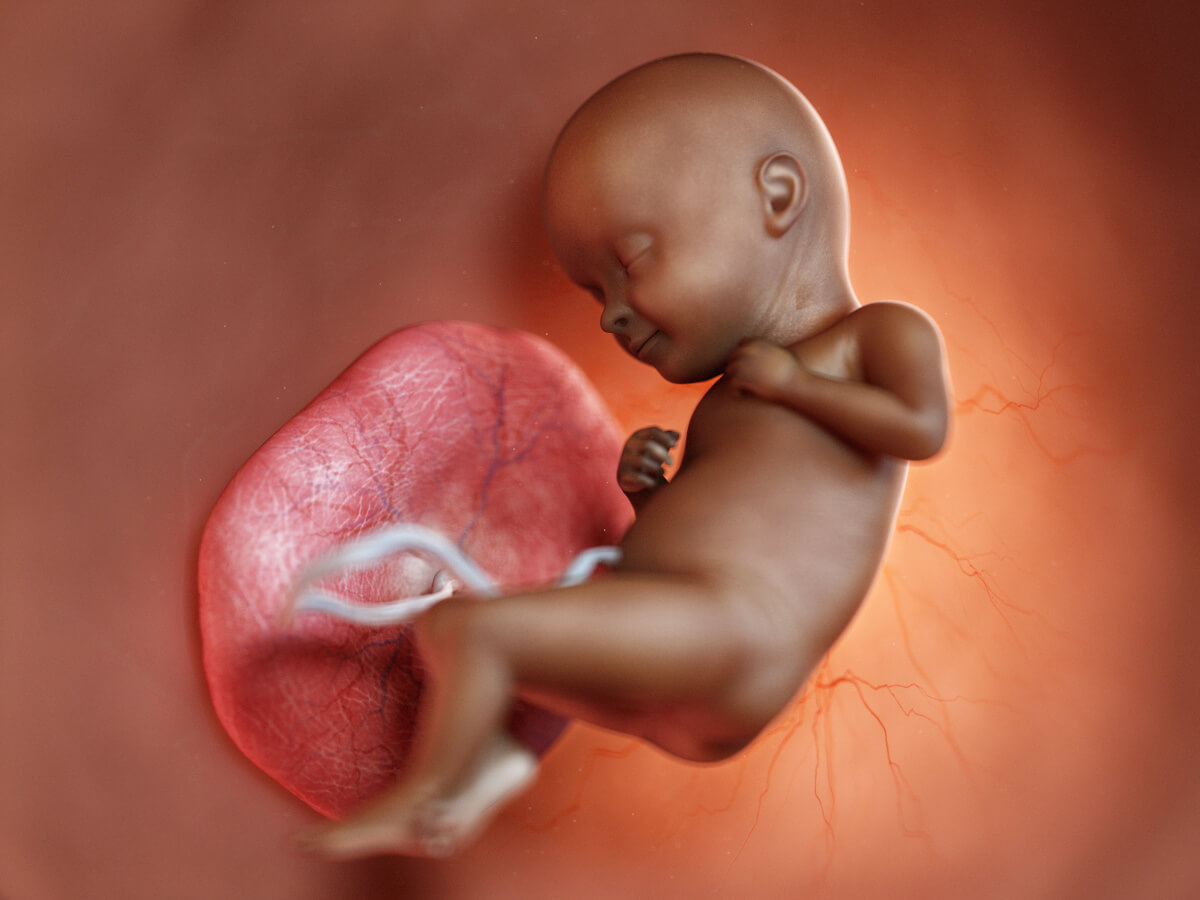

Die Plazenta ist ein sehr wichtiger Bestandteil einer Schwangerschaft. Sie befindet sich normalerweise an der Außenseite der Gebärmutter, wo sie den Fötus mit Nährstoffen, Sauerstoff und Blut versorgt.

Das Organ ist essenziell, um dem Fötus alles zu bieten, was er benötigt, aber noch nicht selbst produzieren kann. Die Plazenta übernimmt die Aufgaben eines Ernährungssystems, indem sie Nährstoffe an den Embryo liefert und Abfallprodukte absondert.

Ferner beteiligt sich die Plazenta am Austausch von Sauerstoff und Kohlenstoffdioxid sowie hormonelle Regulationen. Mit anderen Worten generiert sie alles für den Embryo, worauf der Organismus von Mutter und Fetus angewiesen ist.

Während Dein Baby munter vor sich hin wächst, bildet sich eine feine Membran. Diese ermöglicht nicht nur den Stoffaustausch, sondern schützt den Fötus auch vor Deinem Immunsystem. So ist Dein Kind rundum geschützt und kann beruhigt mit seiner Entwicklung beginnen.